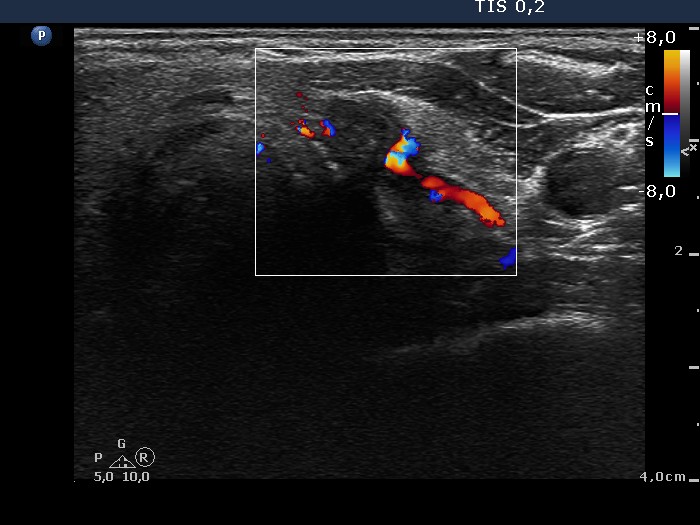

Extrathyroidal spread - case conp 032 (ultrasonographic picture 9)

Lower third of the left lobe, transverse scan, color Doppler mode. The vascularization is not specific.